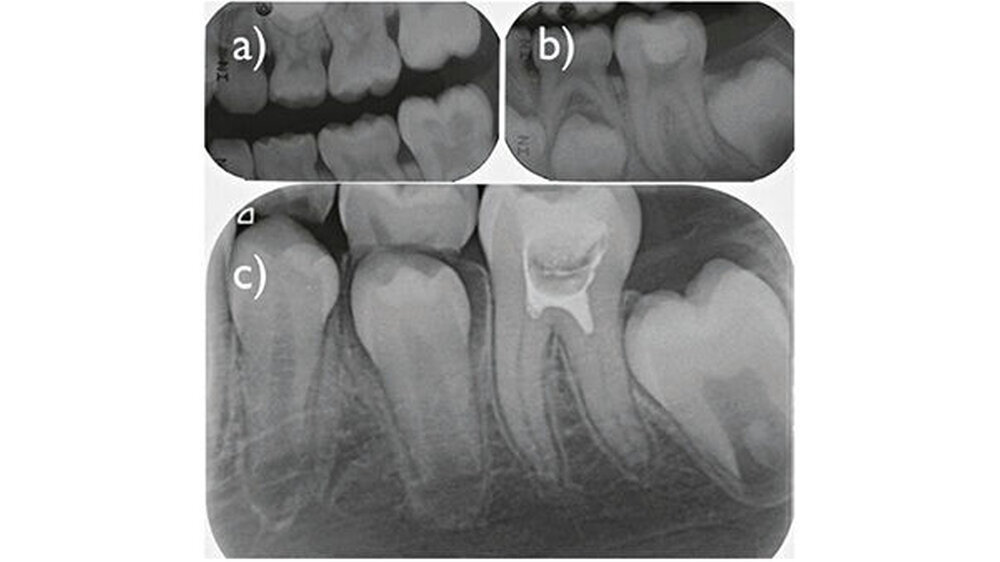

Es ist das Ziel dieser Arbeit, die Behandlungsmöglichkeiten beim bleibenden Zahn mit einer Karies, die radiologisch nahe an den Pulpenraum reicht (Abb. 1), kritisch zu untersuchen und gegeneinander abzuwägen. Insbesondere wurden zwei Parameter analysiert:

Bezüglich der Diagnose "irreversible Pulpitis" zeigten Ricucci und Mitarbeiter in einer kürzlich erschienen Arbeit, dass bei Verwendung definierter Kriterien sehr wohl eine Übereinstimmung zwischen der klinischen und der histologischen Diagnose bestehen kann(Ricucci et al. 2014). Spontanschmerz war hier das Leitsymptom: Wenn ein tief kariöser Zahn spontan und dauernd schmerzte, war auch die Pulpa in 27 von 32 Fällen derart entzündet, dass ein Vitalerhalt ohne zumindest der Entfernung der koronalen Pulpa (Pulpotomie, Abb. 1) unwahrscheinlich bis unmöglich schien. Diese Studie scheint klar darauf hinzuweisen, dass tief kariöse Zähne mit Spontanschmerzen endodontisch behandelt werden müssen.

Trotzdem lassen sich drei unterschiedliche Konzepte abgrenzen (Abb. 1):